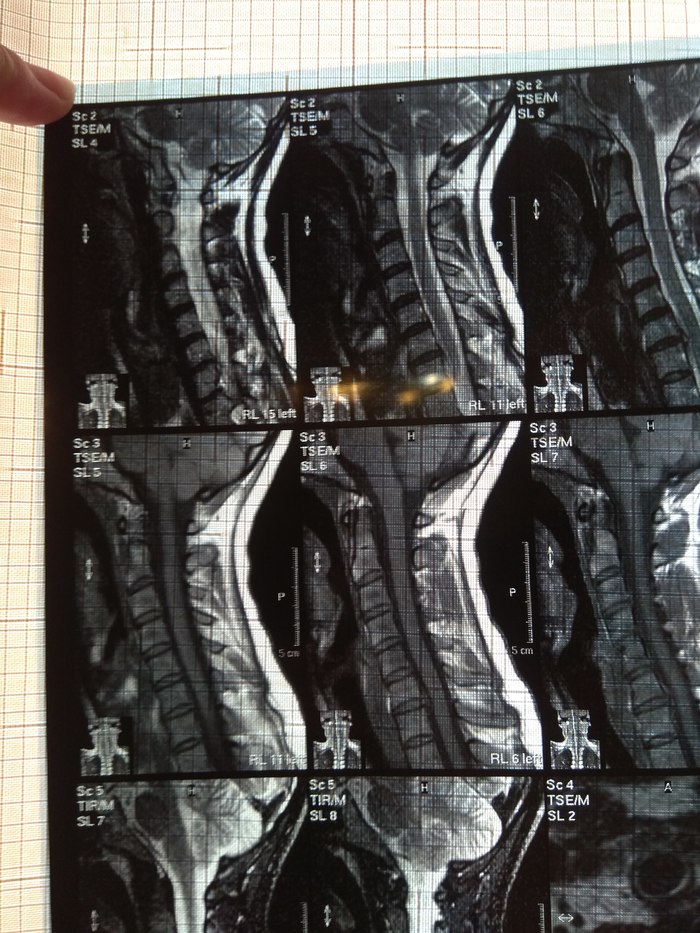

У подруги случилась проблема, тянула с визитом к врачу и в итоге потеряла сознание, вызывали скорую и направили к неврологу. Онемение пальцев на правой руке, сильные боли до судорог и потери сознания. В итоге невролог направил на МРТ и к нейрохирургу, выписали ношение ортопедического воротника, 2 вида уколов и таблетки, названия навскидку не помню. Сказали если через 10 дней не полегчает, то на операцию. Сегодня 5й день, никаких улучшений, рука с каждым днем выше немеет, но подвижность пока в норме. В день по 2-3 раза колет кетонал. Я вот переживаю как бы рука не отказала. Такое может случиться?